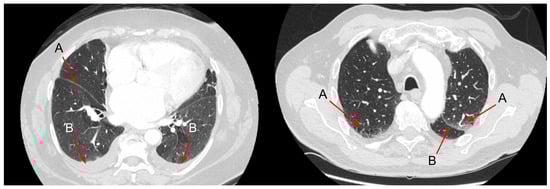

4. Chest CT